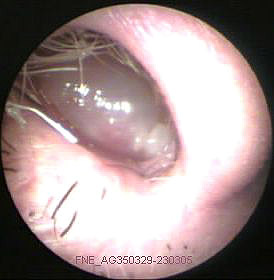

JFC Colesteatoma retrotimpánico.